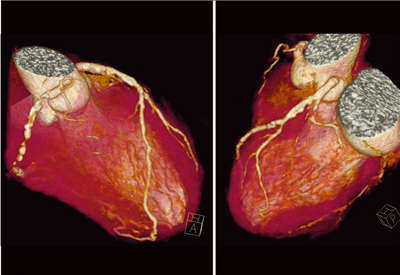

心拍数50〜111bpmと変動が大きかったが,冠動脈はきれいに描出され,RCAとLCXの狭窄が示唆された(図1)。curved MPR画像(図2)では,RCAはほぼ閉塞し,LCXにも強い狭窄が見られた。LADは石灰化のため,はっきりとした評価が難しかった。

![]() 図1 症例1:冠動脈CTのVR画像 |